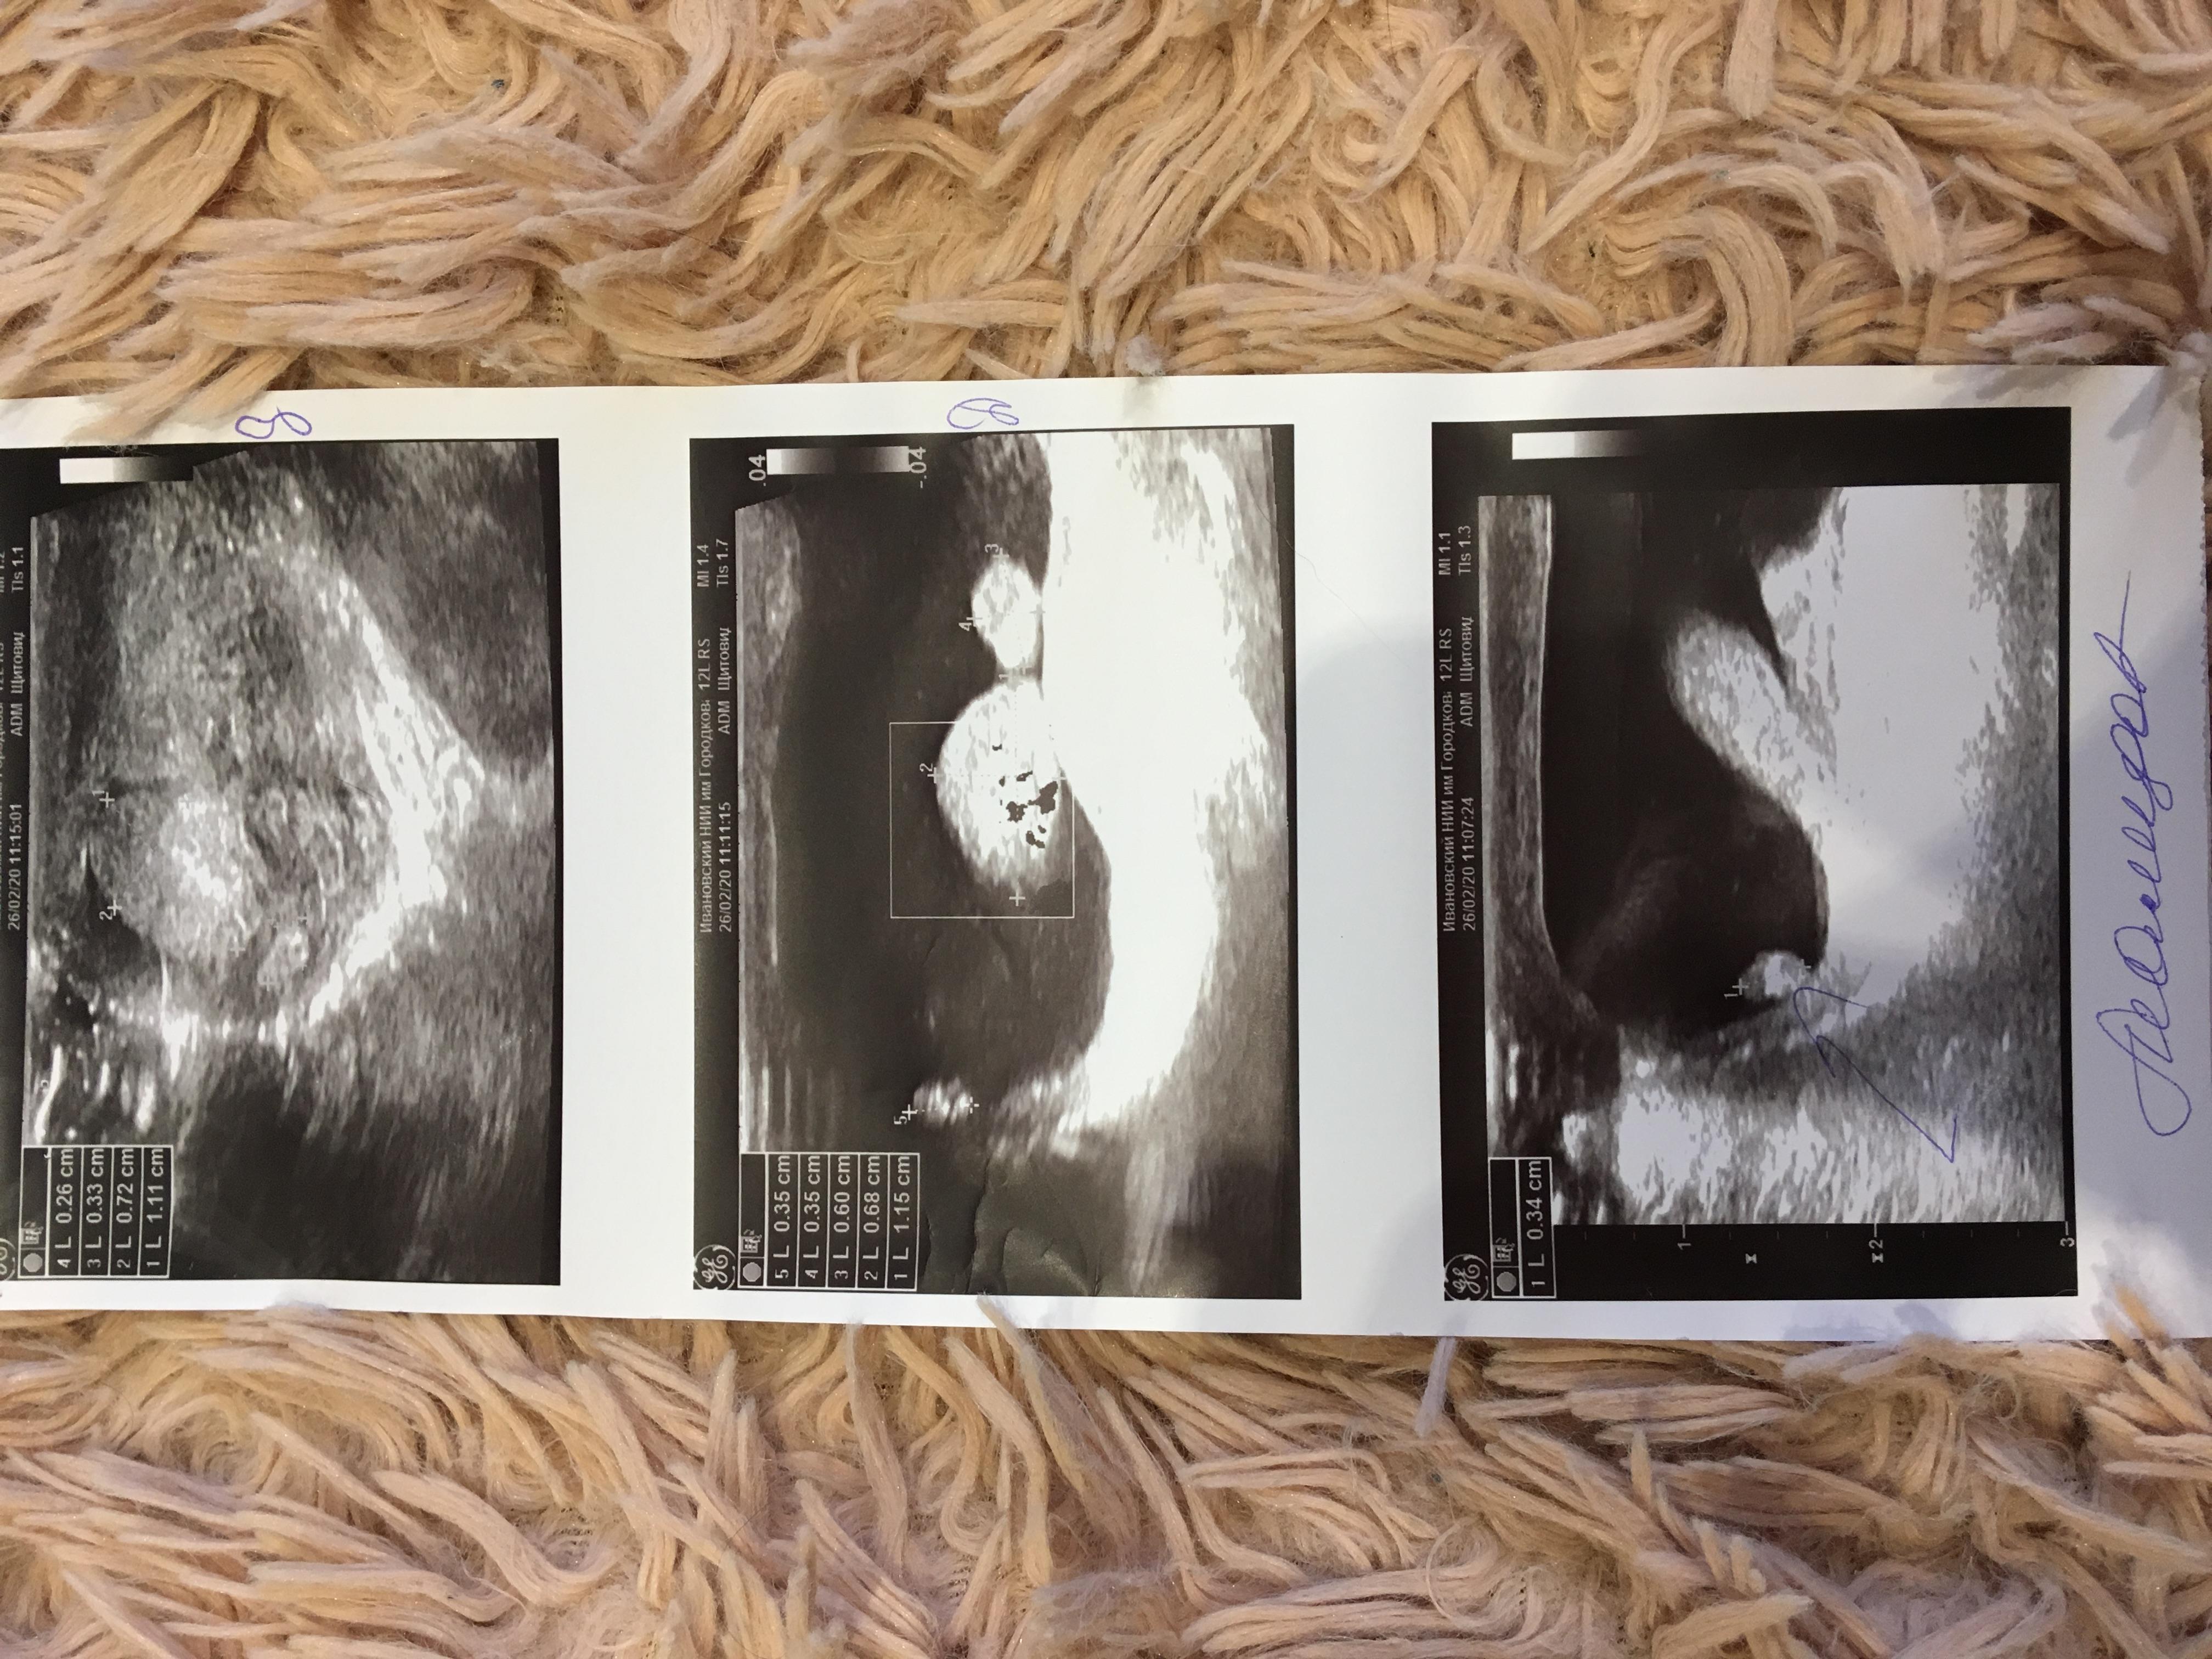

При рождении у сына обнаружили водянку правого яичка. На 3й день яичко посинело, отправили на узи. В итоге образование на оболочке мошонки(возможно полип) т.к. имеет кровоток.

Прилагаю расшифровки узи

Здравствуйте! В заключении в первом листке имеется указание на перекрут гидатиды справа. Часть заключений нечитабельна. Вам стоит очно обратиться к неонатологу и детскому урологу. Удачи!